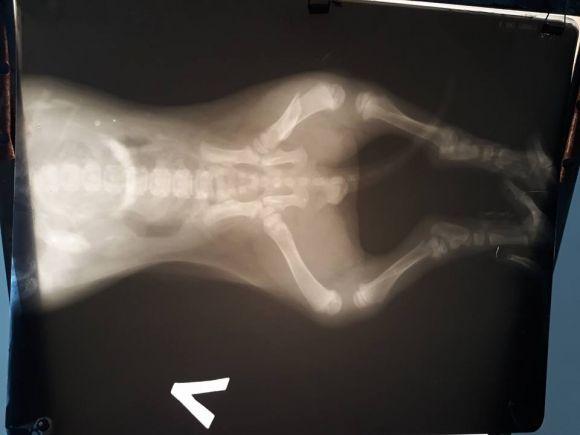

Потім активісти об’їздили декілька лікарів, зробили рентген.

«За таксі заплатила 190 грн, за рентген 200 грн . У цуценя перелом правої лапки та тріщина у лівій. Зателефонувала на лінію скарг, поскаржилась на цього водія. Йому дали мій номер, подзвонив та возмущатися почав. "я її не бачив, помогти не міг і т д.". Як сказала, а хто буде оплачувати? Засміявся!!!!», – розповідають активісти.

Згодом лікар зробив операцію і склав лапку.